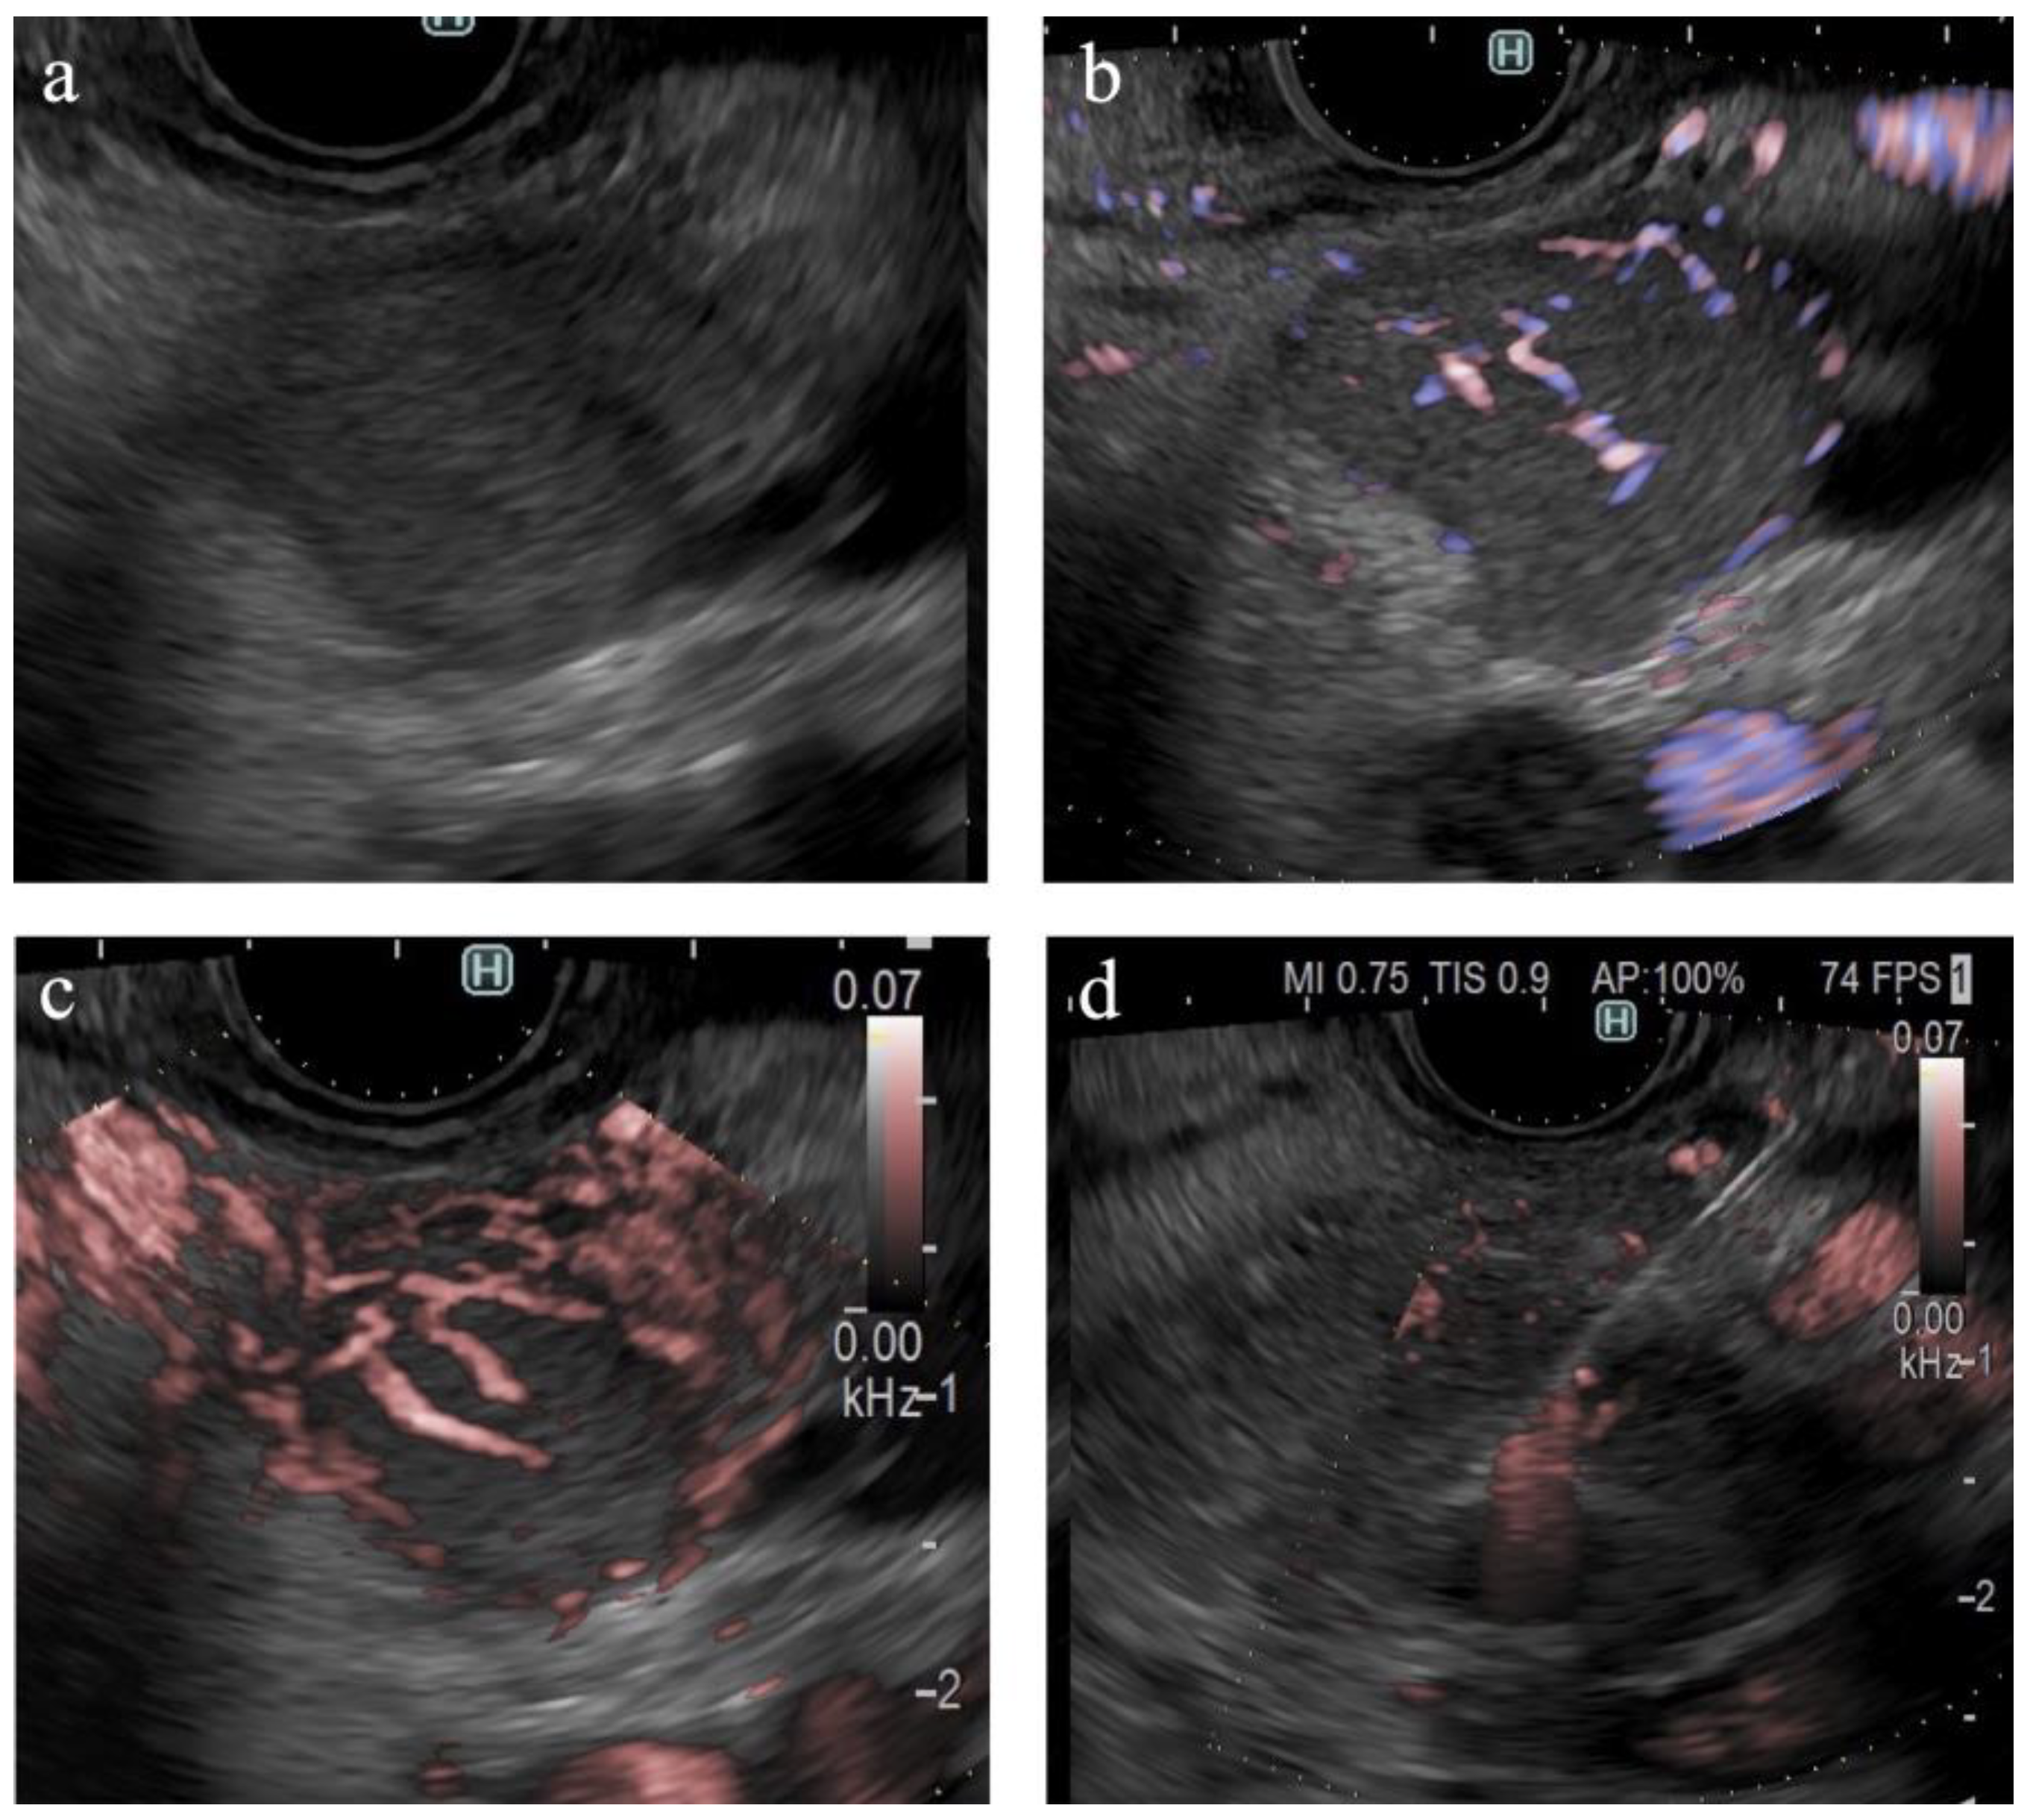

Figure 6.

A case of pancreatic neuroendocrine neoplasm. (a) B-mode shows a hypoechoic tumor with a well-defined margin. (b) eFLOW shows linear vessels in the lesion. (c) On DFI, the tumor is occupied by dilated vessels. (d) Endoscopic ultrasound-guided tissue acquisition.

The findings of this study demonstrate the utility of DFI for purposes other than the differential diagnosis of SPLs. DFI enabled the identification of small hypervascular lesions within 10 mm, which was unexpected (Figure 4c,d). The frame rate of DFI is higher than those of B-mode and eFLOW; thus, DFI can be used as a screening evaluation for patients with Multiple Endocrine Neoplasia type 1 or von Hippel–Lindau disease [41,42]. Hypersensitivity to vascular structures aided the avoidance of thick vessels during the EUS-FNB procedure (Figure 5). DFI, rather than eFLOW, can be used to define the vessels more precisely in patients with NEN. This technique enables the effective acquisition of tissue samples without major bleeding. The absence of linear vessels in pancreatic cancer lesions can aid the detection of tumor margins (Figure 6). A pancreatic cancer lesion without a detectable margin was observed on B-mode and eFLOW in this case, and the initial EUS-FNB result was a false negative. Subsequently, DFI was performed, and the normal vessels in the surrounding pancreatic parenchyma near the tumor margin disappeared. The diagnosis was confirmed by puncturing the areas without vessels on DFI. Thus, DFI can be considered a novel tool for determining the differential diagnosis of pancreatic cancer in the future.